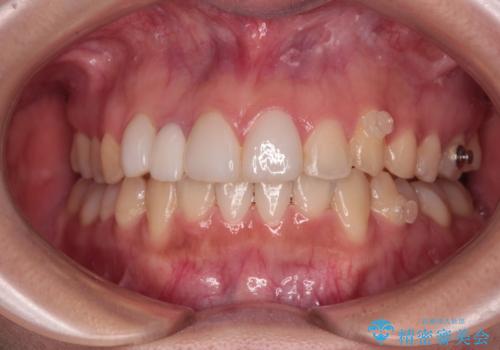

前歯のデコボコが気になる インビザラインによる矯正治療

- 上下前歯のデコボコを気にして来院された患者様です。

インビザラインによる上下歯列の拡大と、IPR(歯と歯の間を削る)にるスペースの獲得により、前歯のデコボコを改善することとしました。

下顎前歯は後戻りを起こしやすいため、舌側を細いワイヤーで固定し、マウスピース型リテーナーで保定を行うこととしました。